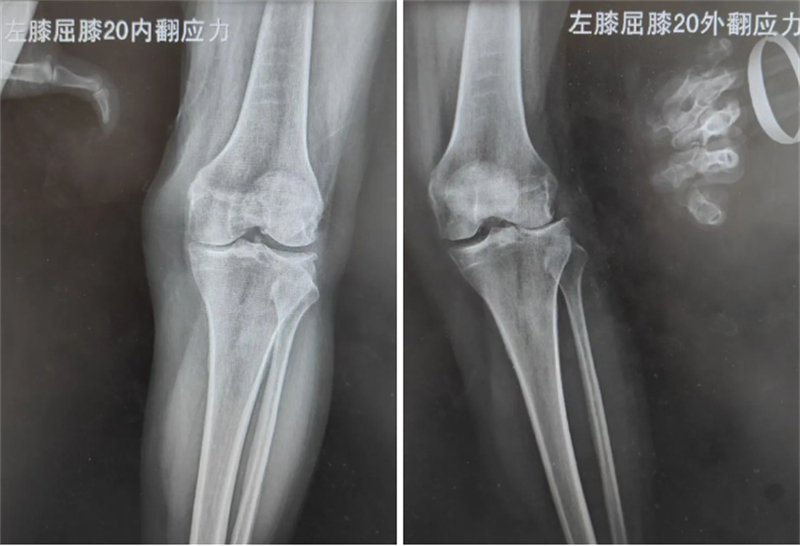

膝關節骨性關節炎是老年人膝關節疼痛的一大病因,困擾無數老年患者,59歲的徐女士就一直被該病困擾,出現膝關節疼痛、行走困難的情況。通過X線及磁共振檢查,醫生發現徐女士為膝關節外側盤狀半月板撕裂后局部常年受應力刺激,關節外側軟骨磨損所致的膝關節外側間室骨性關節炎。考慮徐女士膝關節的韌帶及內側間室軟骨完好,僅為膝關節外側間室的軟骨磨損,科室決定實施膝關節外側單髁關節置換術,在解決徐女士膝關節疼痛的基礎上,盡可能減少正常膝關節結構的損傷,實現術后快速康復、減少疼痛的目的。

醫生介紹,徐女士的這場手術,能否精確完成術前設計,恢復膝關節正常的關節線高度和下肢的力線是手術的重點。術前在手術機器人智能系統上根據患者下肢的CT測量數據進行一系列的3D建模、數據分析、術前計算、術中計劃,最終確定假體的大小、截骨范圍、放置位置等。